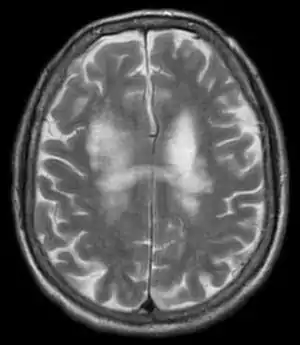

| T2-weighted MRI showing progressive multifocal leukoencephalopathy | |

PML is diagnosed in a patient with a progressive course of the disease, finding JC virus DNA in spinal fluid together with consistent white-matter lesions on brain magnetic resonance imaging (MRI); alternatively, a brain biopsy is diagnostic[1] when the typical histopathology of demyelination, bizarre astrocytes, and enlarged oligodendroglial nuclei are present, coupled with techniques showing the presence of JC virus.[11]

Characteristic evidence of PML on brain CT scan images are multifocal, noncontrast enhancing hypodense lesions without mass effect, but MRI is far more sensitive than CT.[11] The most common area of involvement is the cortical white matter of frontal and parieto occipital lobes, but lesions may occur anywhere in the brain, such as the basal ganglia, external capsule, and posterior cranial fossa structures such as the brain stem and cerebellum.[11] Although typically multifocal, natalizumab-associated PML is often monofocal, predominantly in the frontal lobe.[11]